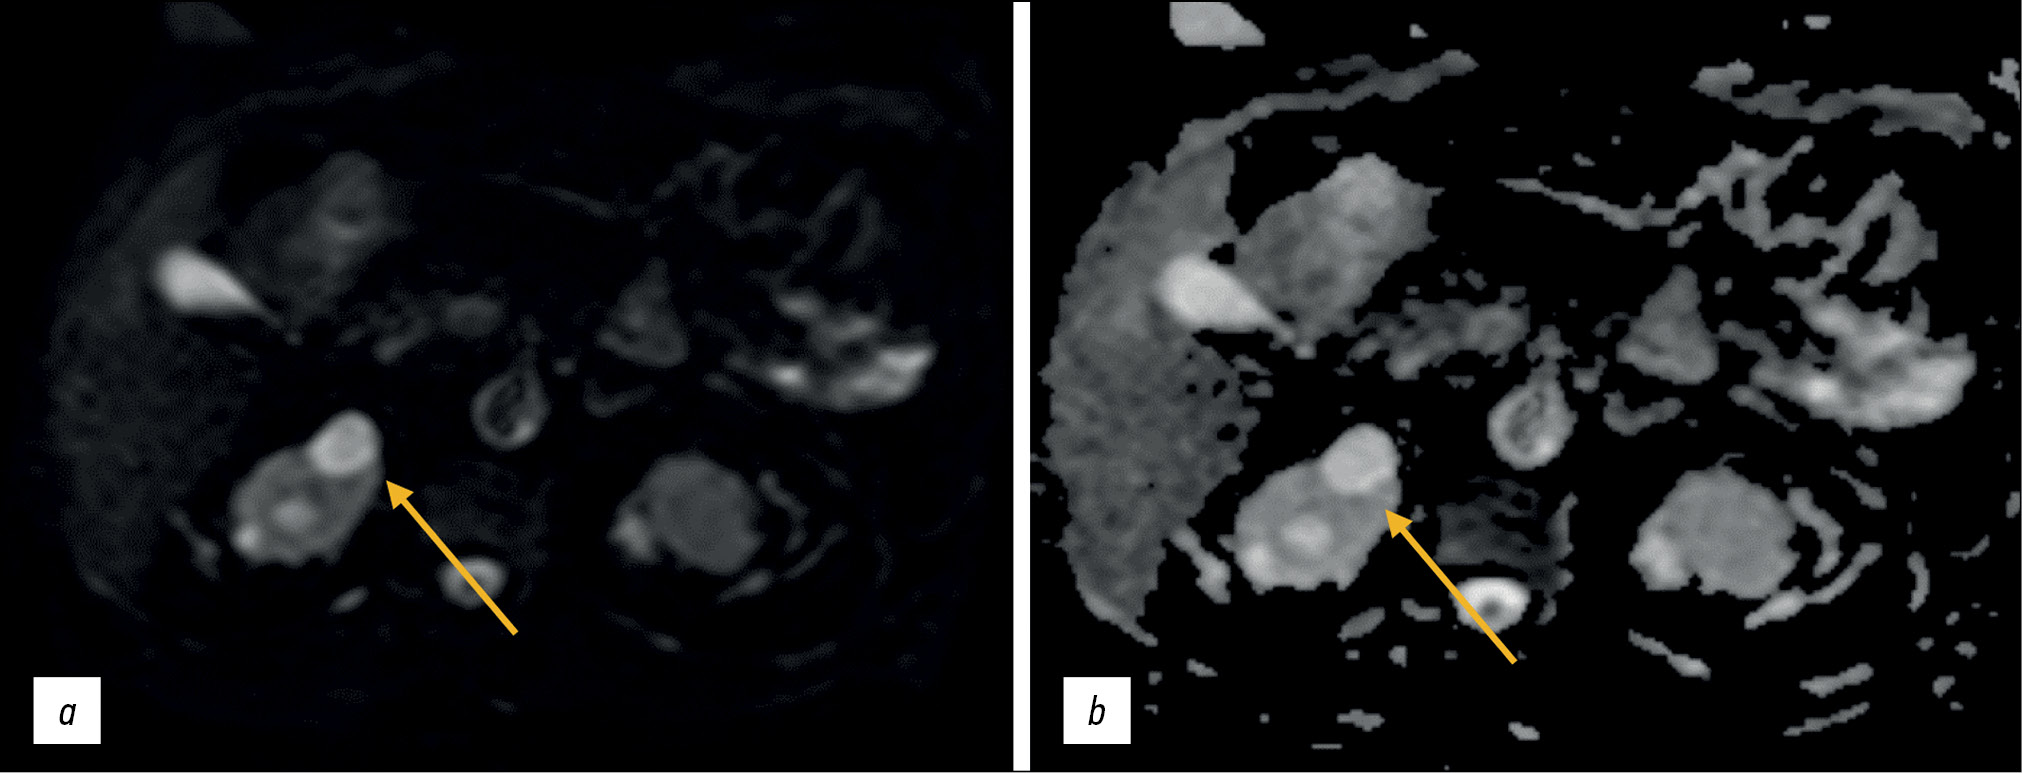

DWIs are based on differences in the movement of water molecules (diffusion) in the extracellular and intracellular spaces and are used for visualization without exogenous contrast agents. This technique allows for quantitative and qualitative analyses of not only cell density but also cell membrane integrity, making it a type of functional image assessment [10]. Therefore, it should be included in standard abdominal and retroperitoneal MRI protocols (Figs. 2 and 3).

Figure 2. Abdominal magnetic resonance imaging, simple renal cortical cysts (arrows): а a diffusion-weighted image; b map of the apparent diffusion coefficient. False restricted diffusion.

Figure 3. Abdominal magnetic resonance imaging, secondary hepatic lesions (arrows): а a diffusion-weighted image; b map of the apparent diffusion coefficient. True restricted diffusion.

DWIs were initially used to diagnose brain pathology, primarily strokes: signal changes in a given pulse sequence allow for the detection of ischemic changes long before they are visible on T2-WIs. DWIs are now used to diagnose various extracranial pathologies owing to advancements in high-amplitude gradients, multichannel surface coils, and parallel imaging.

Diffusion is proportional to cell density and cell membrane integrity: restricted diffusion is observed in tissues with increased cellularity or decreased extracellular fluid volume (e.g., some tumors and abscesses; Fig. 4) and in the presence of cytotoxic edema. Relatively free diffusion is observed in tissues with low cell density or when their membranes are damaged, such as cysts or necrotic tissues.